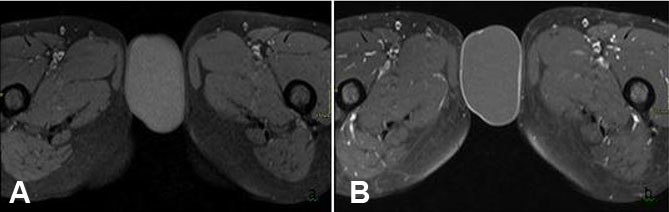

Further evaluation of the mass was undertaken via MRI pelvis—this was conducted via a 1.5 T MR system (the Magnetom Symphony, Siemens Germany). Magnetic resonance imaging examination revealed an exophytic, round to ovoid subcutaneous tissue mass involving the vulvar region, measuring around 61 × 36 mm. It returned hyperintense signals on T2-weighted sequences (Figure 2) and mild hyperintense signals on T1 (Figure 3) with a thin peripheral rim of enhancement on T1 post-contrast sequences (Figure 3). Additionally, the mass showed diffusion restriction (Figure 4). These imaging features were consistent with vulvar epidermoid cyst, and surgical excision was recommended. The patient underwent surgical excision without any complications and histopathology reaffirmed the diagnosis of vulvar epidermoid cyst having a stratified squamous epithelial lining.

Figure 4: MRI images taken on (A) diffusion weighted imaging (DWI) and (B) apparent diffusion coefficient (ADC) demonstrate that the lesion returns high intensity signals on DWI and low intensity signals on ADC, i.e., showing diffusion restriction, which is a characteristic feature of epidermoid cysts.

Magnetic resonance imaging represents a useful modality for further evaluation of epidermoid cysts, as it can differentiate between different cystic masses, provide insights regarding infiltration of adjacent tissues, and give valuable information regarding its location. On MRI examination, cystic structures return hypointense signals on T1 and hyperintense signals on T2-weighted sequences. A key difference between epidermoid cysts and other cystic structures is that the former return hyperintense signals on diffusion weighted sequences and low signals on apparent diffusion coefficient (ADC), i.e., showing diffusion restriction, which is a characteristic feature of epidermoid cysts [8]. These findings were evident in our case too, the cyst showed hyperintense signals on T2 and also showed diffusion restriction [9].